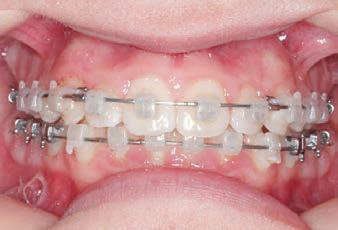

CLASS II DIV.1 - Marra

INITIAL - 4/4/18

PROGRESS 1 - 26/9/18 - Class I platform accomplished in 5.75 months with Motion 3D COLOR Appliance

PROGRESS 2 - 26/9/18 - Placement of the SLX 3D Clear Brackets

with M-ONE .015 Cu Nitanium 27°

PROVIDED BY: DR. LUIS

PROGRESS 3 - 30/10/18 - With M-TWO .020 x .020 Cu Nitanium 35° archwire

PROGRESS 4 - 27/11/18 - 3 links power chain: 5, 4, bypass 3 to crimp hooks

PROGRESS 5 - 13/3/19 - With M-TWO .020 x .020 Cu Nitanium 35° archwire

PROGRESS 6 - 1/8/19 - With M-THREE.019 x .025 Beta Titanium wire

FINAL - 10/10/19 - Appliances removed AFTER

PROGRESS 7 - 10/10/19 - Final day in SLX 3D Clear Brackets BEFORE